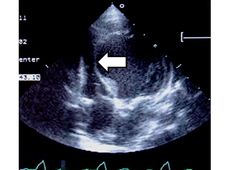

心室中隔が薄くなり瘤のように飛び出して

右室を圧迫しています(矢印)。

これでは血圧も十分でませんし、

心不全が強くて危険です。

手術前の心不全発作の強さがよくわかる写真です。